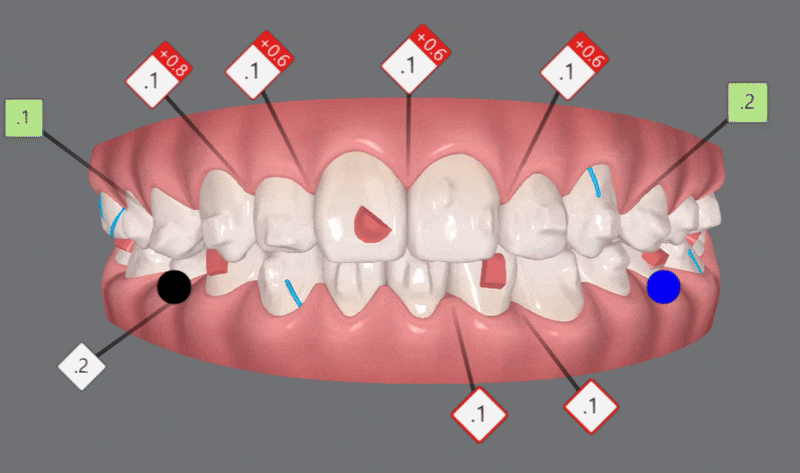

2nd Clincheck(26개 장치)

교정기간: 24/2~ 24/7

첫번째 클린체크에서는 치아 배열에 중점을 두었다면

완벽함을 추구하는 김승우 원장님께서는

두번째엔 좀더 세심한 디자인을 통해

위 아랫니의 교합을 보완해주었습니다.

청소년인비절라인 두번째 클린체크 에서는

첫번째 클린체크에서 어태치먼트가 추가되어

이전의 클린체크를 보완해 교정치료의 완성도를 높여 줍니다.

3rd Clincheck(12개 장치)

교정기간: 24/7~24/11